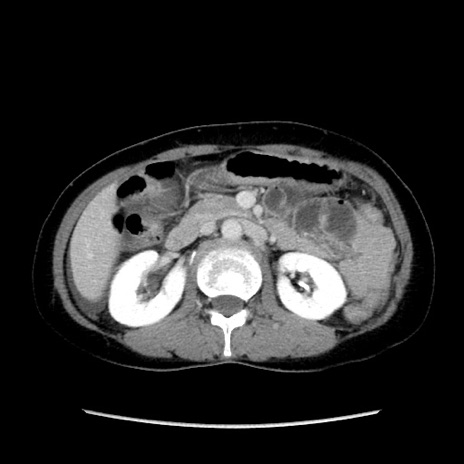

症例32(横断像)

【症例】40歳代 女性

【主訴】上腹部痛、嘔気・嘔吐

【現病歴】約9時間前頃から急に上腹部痛、嘔気、嘔吐が出現。改善しないため救急要請。

【既往歴】子宮頚癌(広汎子宮全摘術、放射線療法)、腸閉塞

【身体所見】腹部:平坦、軟、腸雑音亢進、上腹部を中心に腹部全体に圧痛あり。

【データ】WBC 8400、CRP 0.03